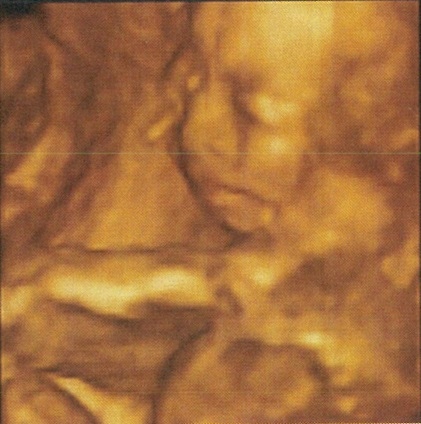

【好孕再到】懷孕23~38週 心路歷程 (高層次超音波、妊娠糖尿病篩檢、百日咳疫苗、預約剖腹、假性宮縮)